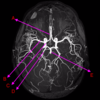

which of the following connects to the external carotid artery?

middle cerebral artery

anterior cerebral artery

posterior communicating artery

menigeal branch

opthalmic artery

which of the following connects to the external carotid artery?

middle cerebral artery

anterior cerebral artery

posterior communicating artery

menigeal branch

opthalmic artery